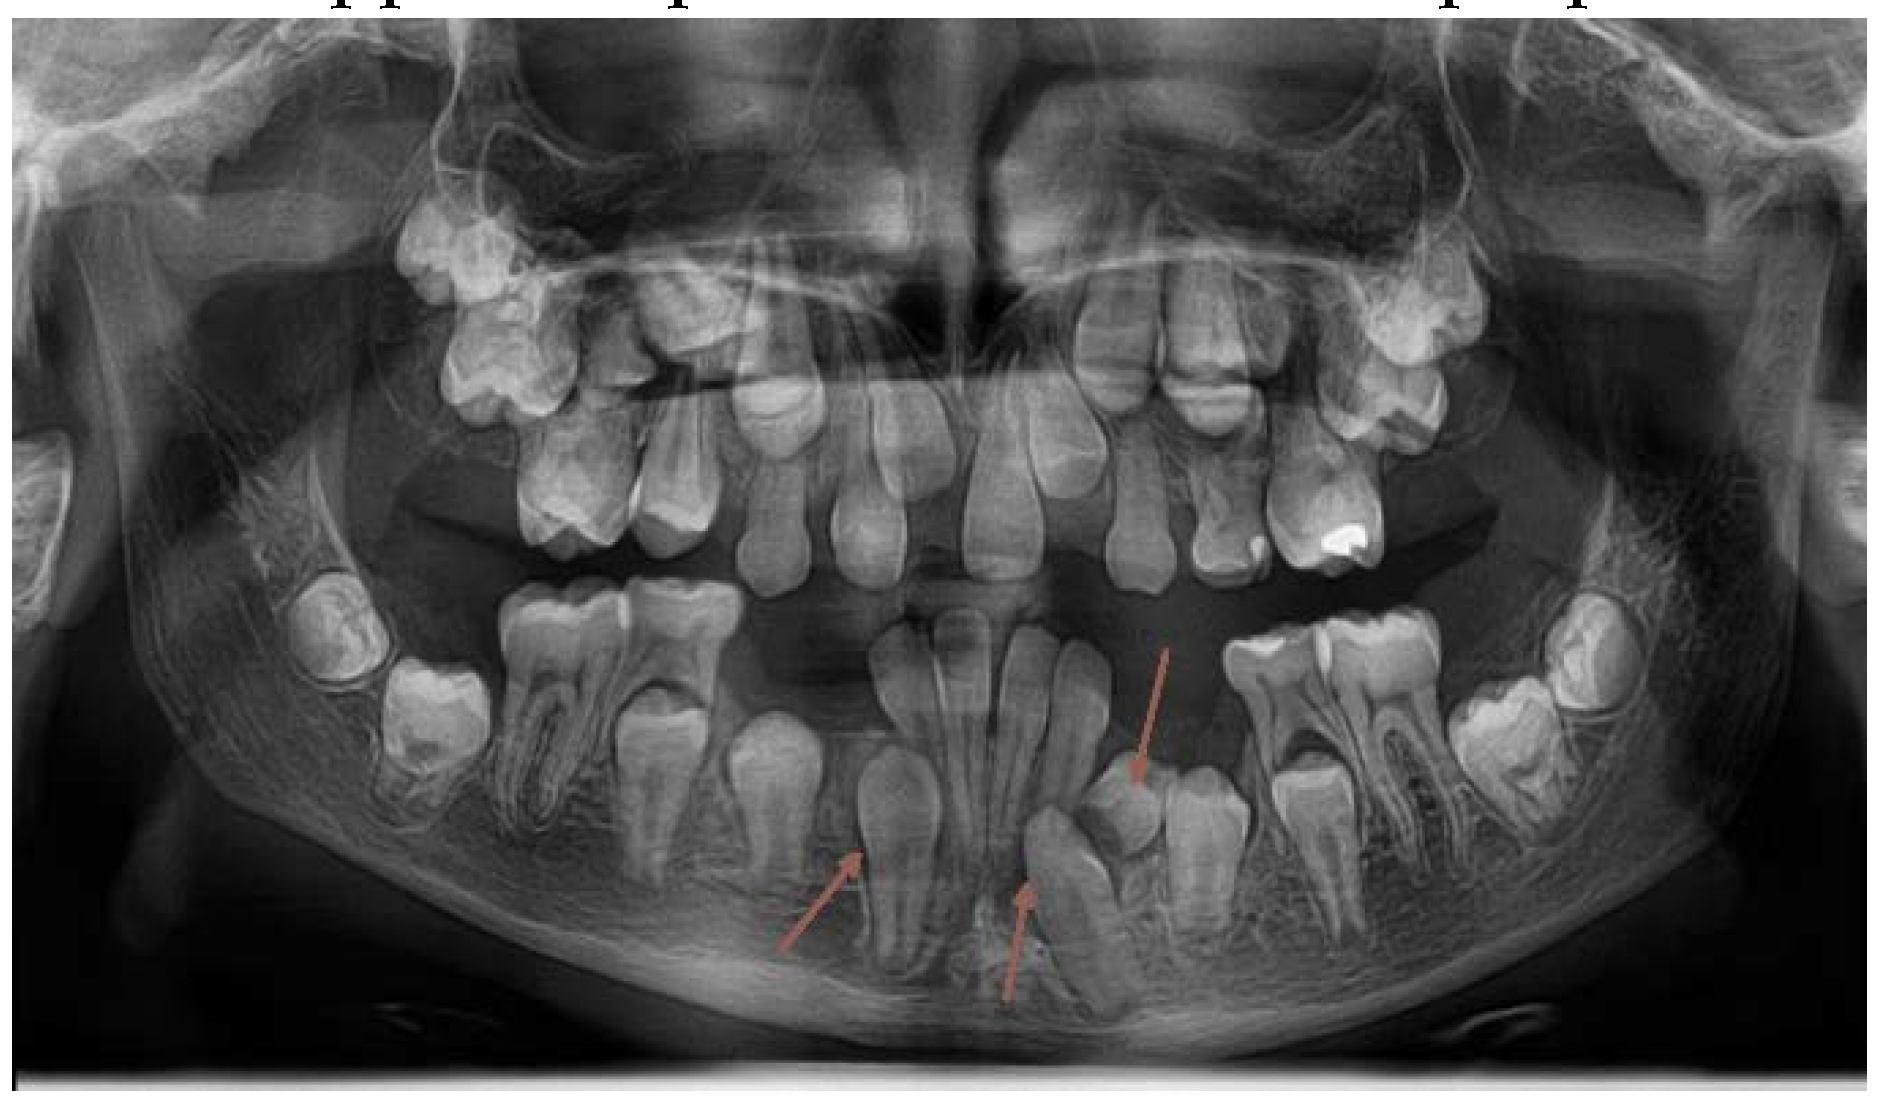

In April 2018, the patient´s age was 13 years 5 months, the dental age was 8 years. Under general anesthesia, two supernumerary teeth in the lower right and one in the lower left quadrant were extracted. (Figure 5.,10.) 3 primary teeth were extracted as well (73,83 and 84). This cleared the way for the anticipated spontaneous eruption of lower canines and first premolars. (Figure 10.) One supernumerary tooth with an underdeveloped root in the area of 35 was subsequently extracted from the chair under local anesthesia. (Figure 10.) Unfortunately the path of eruption of the 33 and 43 was too close to the apical area of the 42 and 32, (Figure 10, 11.), so an additional surgical intervention was planned, in local anesthesia, to expose the lower canines and redirect their eruption. This required already a fixed orthodontic appliance placement to anchor proposed lower canine traction.

Figure 10. OPG x-ray after the 2nd surgical intervention under general anesthesia. (2018).